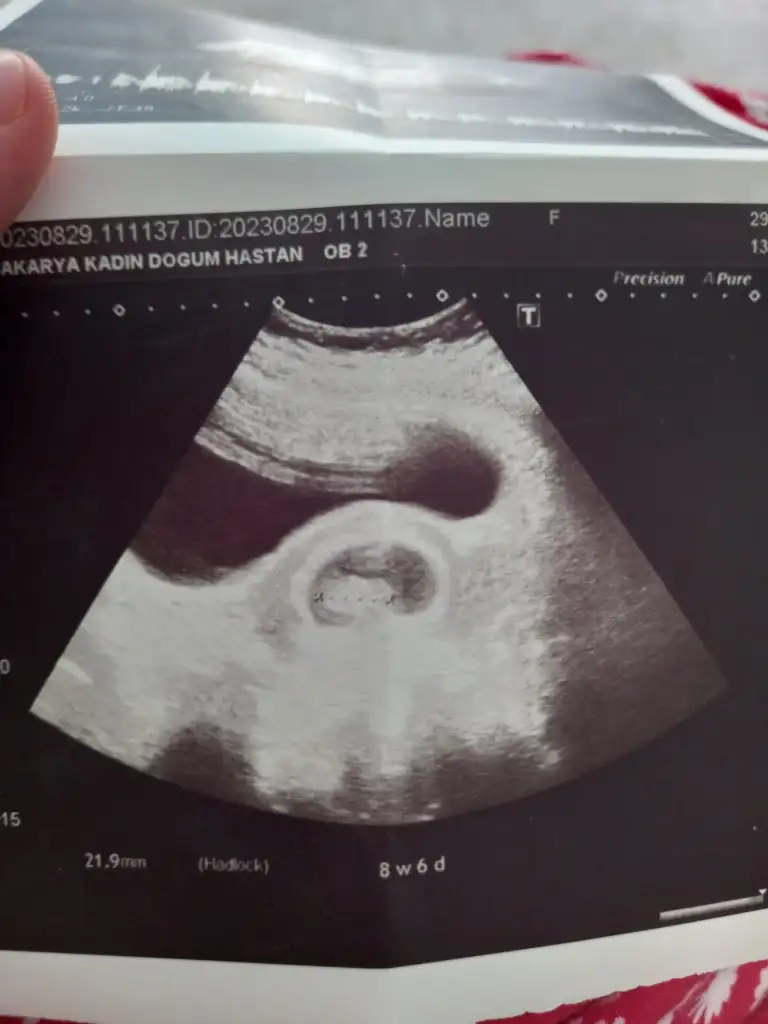

Nerden anladınız

Daha hiçbir şeyi oluşmamış, el ayak kafa kol vs. Benim 9 haftada her şeyi belirgindiNerden anladınız

O zman sizinki erkekti daha çabuk oluşum gösterirler.Daha hiçbir şeyi oluşmamış, el ayak kafa kol vs. Benim 9 haftada her şeyi belirgindi![]()

Aynen canım benim erkek, erkekler daha çabuk oluşuyor. Tabi istisnalar da var, ama yine de kız diyorumO zman sizinki erkekti daha çabuk oluşum gösterirler.![]()

Canım,benim ki belli olmuyor mu? Bi bakar mısın?Aynen canım benim erkek, erkekler daha çabuk oluşuyor. Tabi istisnalar da var, ama yine de kız diyorumsağlıkla ve gönlünce inşallah

Kaç haftalık ve karından mıCanım,benim ki belli olmuyor mu? Bi bakar mısın?

6+3 karından canimKaç haftalık ve karından mı![]()